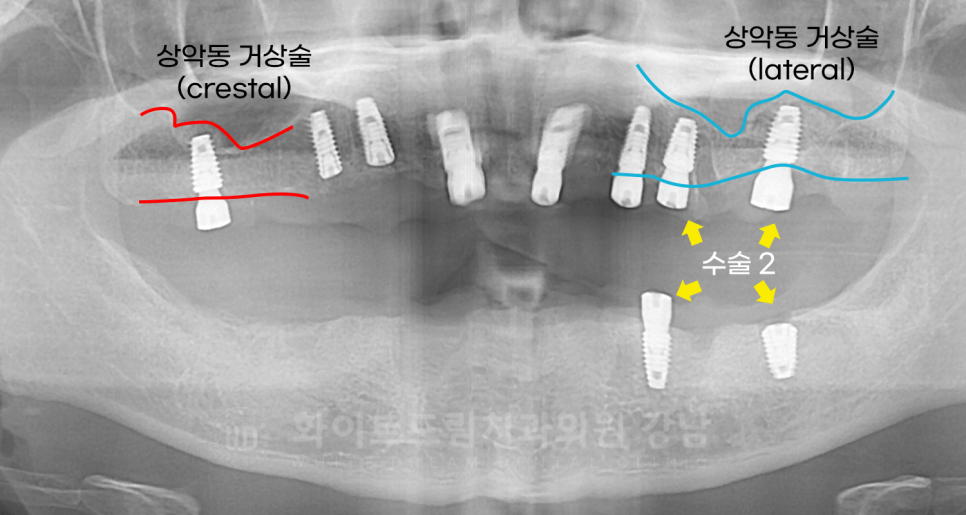

임플란트는 총 3회에 걸쳐 부분적으로 진행했습니다.

수술 1) 10번대 수술 (20.04.04)

16, 14, 13, 11, 21, 23, 24 번 임플란트를 식립했고,

이중 16번은 상악동 거상술 (crestal)을 이용하여 부족한 잇몸뼈를 보강했습니다.

수술 2) 20번, 30번대 수술 (20.04.18)

24, 26, 34, 36번 임플란트 식립과 lateral 방식의 상악동 거상술 수술을 진행했습니다.

수술 1차에서 16번 치아도 상악동 거상술을 진행했는데, 술식이 다르죠?

16번은 crestal 방식을 이용했고

24, 26번은 laterla 방식을 이용했습니다.

치료 후 x-ray를 보면 식립된 뼈의 양이 다른 것이 한눈에 보이실 겁니다.

잇몸뼈가 너무 얇거나 없는 경우,

구강 내 구조물로 인해 수술이 어려울 것으로 판단되는 경우는

lateral 방식을 이용하는데, 뺨쪽 잇몸에 창(window)을 내어 진행하는 방식입니다.

당연히 난이도는 crestral >>>>>>>>>>>>>>>>>lateral입니다.

(그래서 lateral 수술 경험이 많은 의사는 cesrtal 수술은 눈 감고도 한다.. 뭐 이런 말도 있답니다. ^^;)